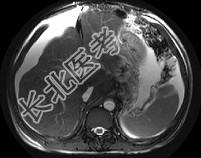

- 单项选择题男,44岁, 有乙肝病史,现腹胀, 右上腹痛,消化不良, 消瘦、乏力、贫血、黄疸,血清转氨酶升高, 清蛋白/球蛋白比值倒置。CT、MRI检查如下图,最准确的诊断是 ( )

A、肝硬化并腹水

B、肝硬化并腹水、再生结节

C、肝硬化腹水、肝癌

D、肝硬化并再生结节

E、肝硬化并腹水、脂肪肝